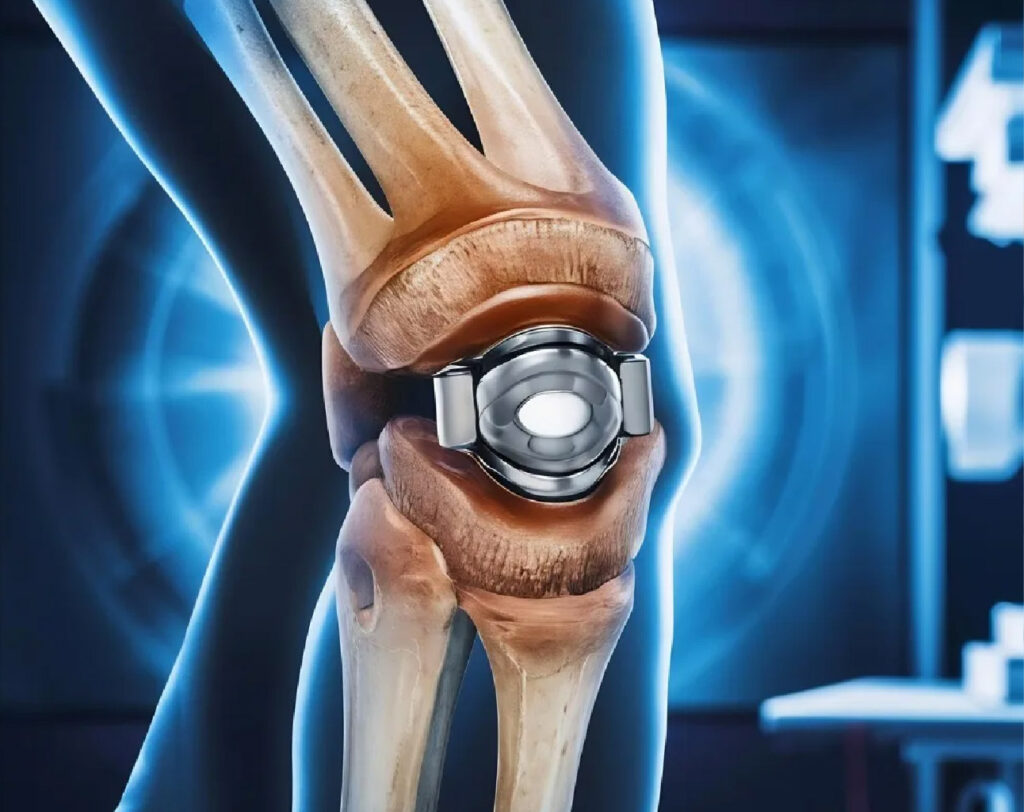

The introduction of Mako SmartRobotics™ has completely changed the way orthopedic surgeries are performed in terms of surgical accuracy and innovation. Mako, a revolutionary device in the medical field, combines robotic technology with surgical expertise, thereby improving the precision and effectiveness of surgery—especially in joint replacements. With its potential to benefit both patients and surgeons, it marks a transformative advancement in joint replacement practices and overall patient care.

During the procedure, the robotic arm helps the surgeon make exceptionally precise bone cuts and guides the placement of the implants—often to within a fraction of a millimeter. This level of accuracy is difficult to achieve manually and is crucial for the joint’s function and longevity.

The robotic system helps the surgeon remove only the damaged parts of the bone while preserving as much healthy bone and soft tissue as possible. This reduces blood loss and post-operative pain.

The precise alignment and positioning of the implant with robotic assistance reduce wear and tear over time. This can potentially extend the life of the joint replacement and lower the need for future revision surgery.

When the implant is perfectly aligned and balanced with the surrounding soft tissues, the new joint often feels more natural to the patient.

The robotic arm aids in executing the pre-planned surgical actions with a level of precision that is difficult to achieve through traditional or conventional methods.

Mako provides real-time data and feedback throughout the surgery, allowing for adjustments and ensuring that the planned procedure aligns with the actual condition. This enhances precision, perfection, and accuracy, which ultimately guarantees the best outcome.

The robotic system constrains the instruments within the planned boundaries, allowing millimeter-level accuracy.